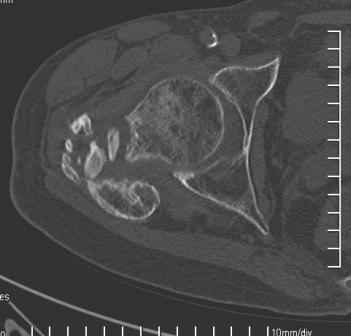

Больной Н. 44 года травма 1,5 года назад июнь 2008 года чрез-под вертельный перелом правого бедра. Во время лечения у больного развился алк. делирий, проводилось консервативное лечение перелома.

Беспокоят боли, укорочение конечности.Укорочение 3 см. Ногу поднимает, сгибание ограничено, ротационные движения в полном объеме.На КТ перелом сросся за счет костной мозоли.Что делать?

Уважаемый Глеб, боли из-за ложного сустава шейки бедра. Сращения там нет.

Тазобедренный сустав сохранный и возраст пациента позволяет побороться. Согласен с Максимом, попробуйте остеотостеотомию.

Уважаемый Глеб! Укорочение наверное побольше, да и наружно-ротационная установка скорее всего присутствует. Суставная щель прекрасная, головка живее всех живых. Ратую за подвертельную с латерализацией: исключает нарушение механической оси («исключает вальгус в коленe»), максимально удлиняет без натяжения m.iliacus. Для иллюстрации остеотомия-переделка (слава богу не автопеределка) у мужчины 65 лет.